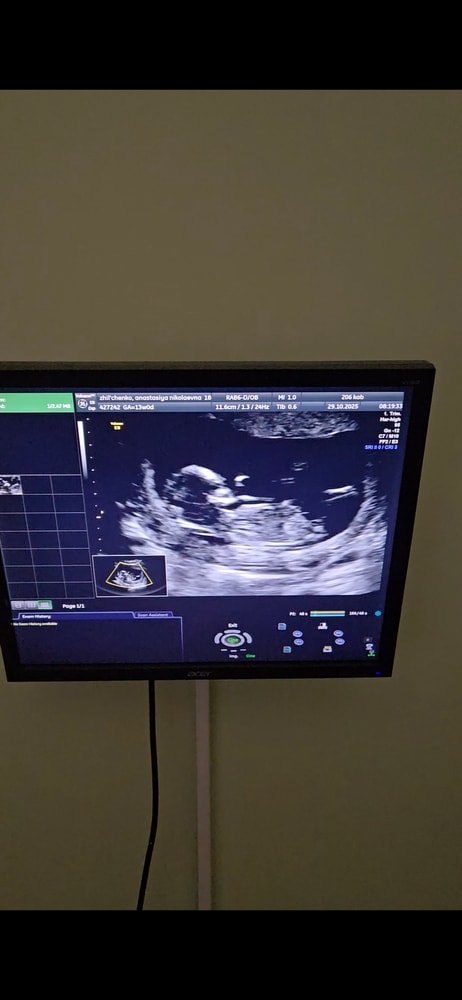

Мальчик/девочка?

Анализы, скринингиХотелось бы послушать знатоков по половым бугоркам 😄 если видно, подскажите) с видео сделала фото

Не понятно - то ли ножка, то ли бугорок. Пока похоже на мальчика.

У меня оба раза гадание по бугоркам совпадало + интуиция не подвела.